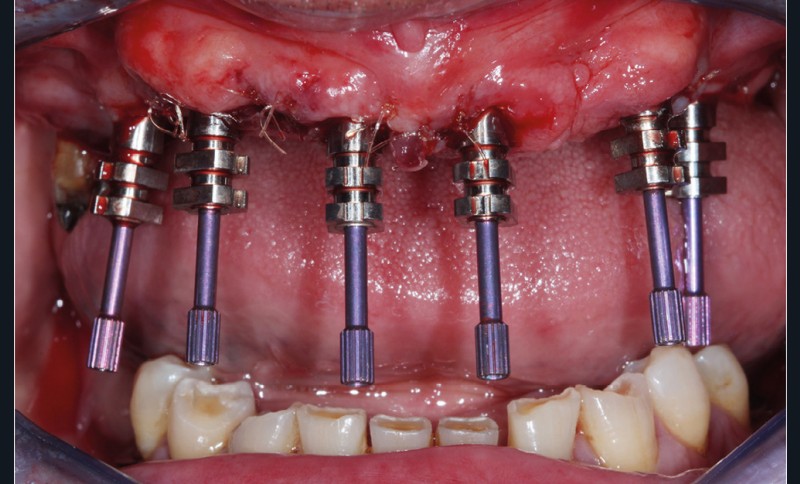

Réévaluation (mars 2022)

Le patient a été satisfait de l’immédiateté et du confort de la restauration provisoire, mais n’a malheureusement pas poursuivi son traitement et n’est venu consulter que quelques années plus tard, avec des répercussions prévisibles et néfastes. L’absence de calage molaire, l’hygiène déficiente (aucun passage de brossette dans les embrasures) et une absence de suivi au cabinet ont entraîné une inflammation très importante des tissus péri-implantaires (fig. 8…